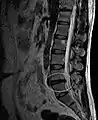

L'imagerie par résonance magnétique peut montrer la hernie, le canal vertébral, les nerfs, les tissus environnants. Les tissus mous sont les mieux analysés par cet examen qui est le plus performant pour le diagnostic de hernie discale. Les images pondérées en T2 montrent clairement la hernie.

IRM lombaire sagittale montrant une hernie discale de niveau L4-L5. IRM lombaire sagittale montrant une hernie discale de niveau L4-L5.

IRM lombaire sagittale montrant des protrusions discales. IRM lombaire sagittale montrant des protrusions discales.